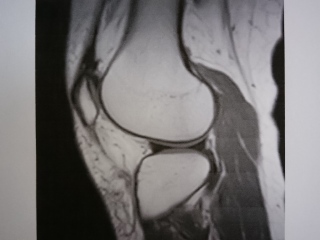

検査結果は・・・

検査技師の所見は、「明らかな損傷は認められません」とのこと。

でも、先生は〜

実際、映像を見せてもらって、ぐりも、ナルホドと思ったけど、

ぐりの痛みがある部分に、影(?)があって・・・

多分、そこから痛みが出てると思われるとのこと。

これ以上、詳しく調べるには、膝に内視鏡を入れるしかないらしい。

とりあえず、2ヶ月くらい注射を続けてみましょうって。